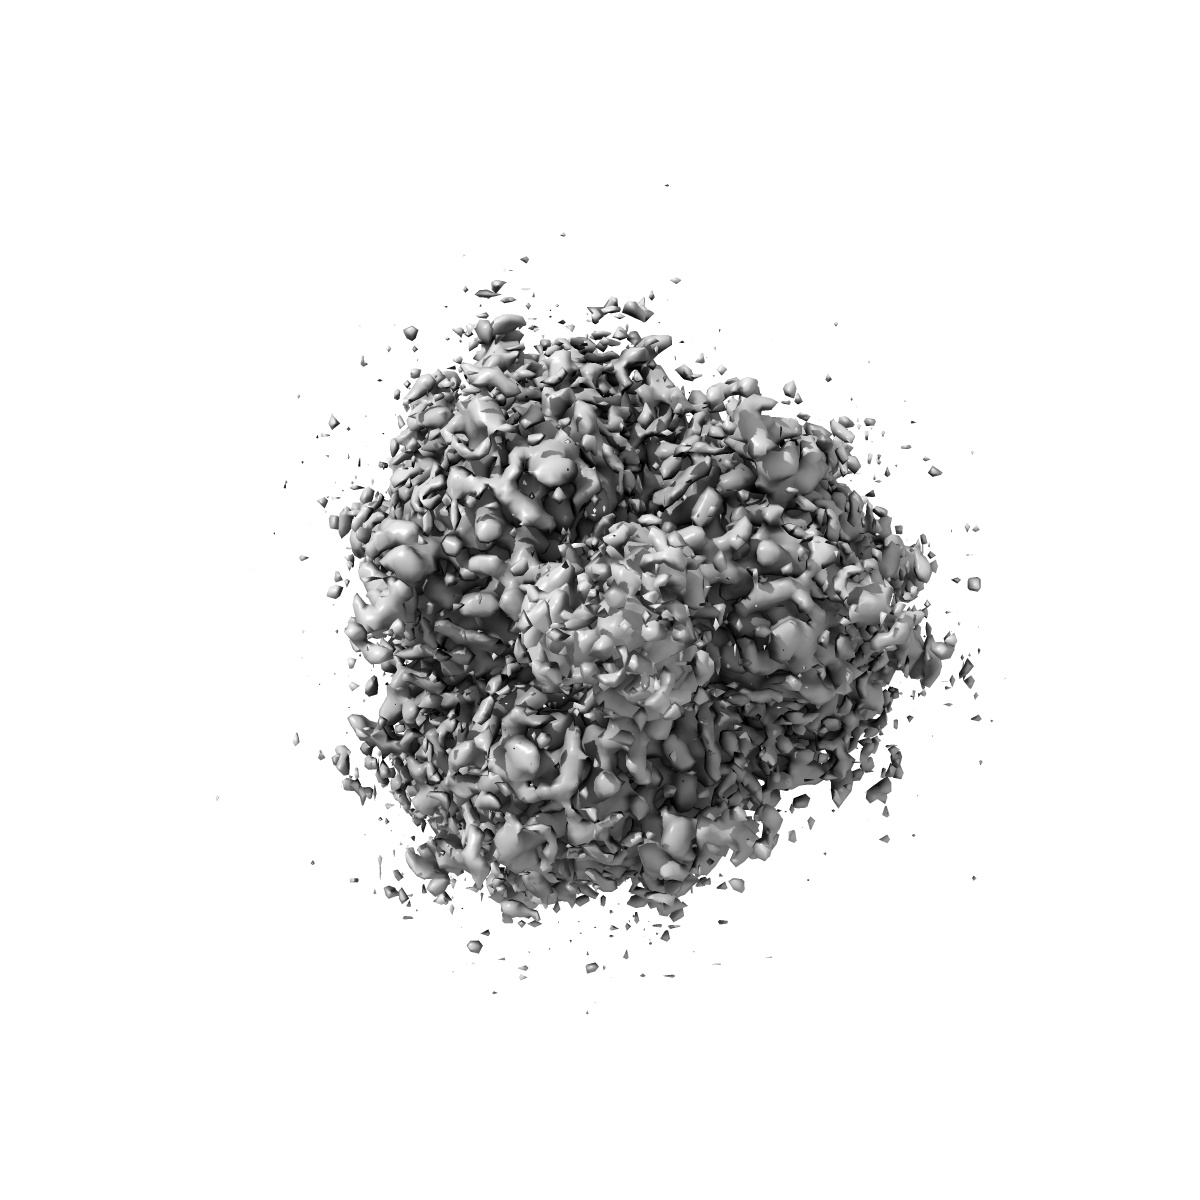

Prefusion stabilized structure of the SARS-CoV-2 fusion machinery

Sample: Prefusion stabilized structure of the SARS-CoV-2 fusion machinery

A broadly generalizable stabilization strategy for sarbecovirus fusion machinery vaccines.